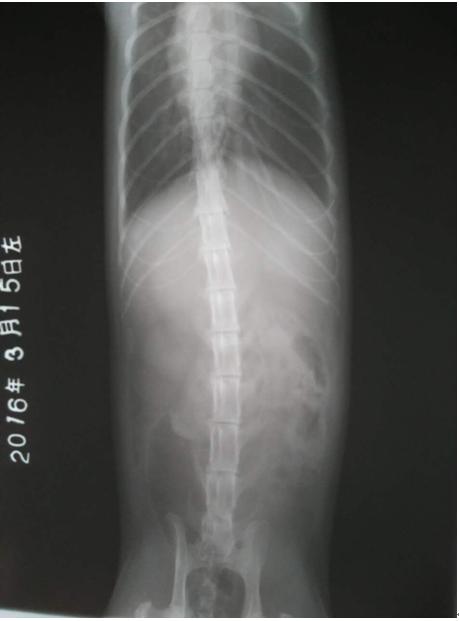

猫加肥,6m,雌性。最近小便带血,遂来院就诊。

从临床表现的主要症状,结合辅助检查结果初步诊断为出血性膀胱炎并结晶尿。

3、在条件允许的情况下,应定期对患猫做X射线、B超复查, 以便了解该病的预后状况,若出现异常情况要及时做出适当的处理。